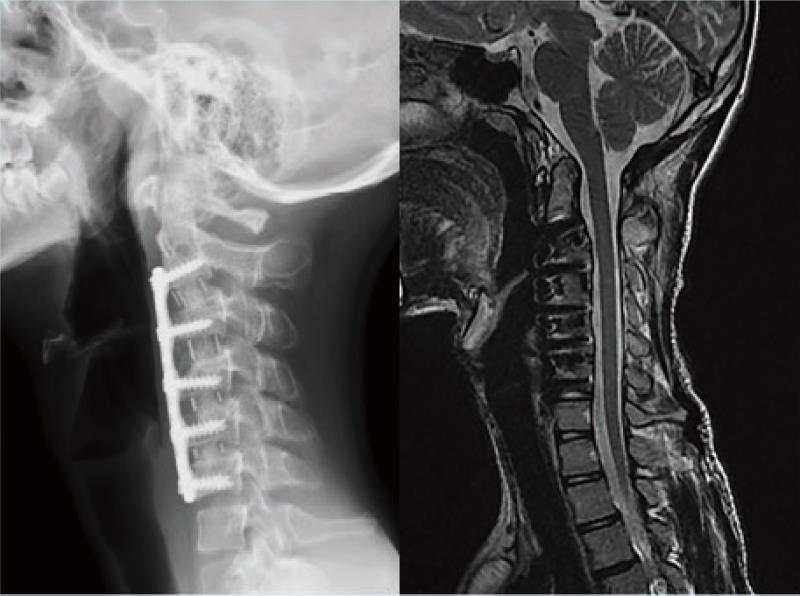

病例2 :颈椎后凸畸形矫形术

颈椎后凸畸形 颈椎前路C2-6椎间盘切除,后凸矫形术。术后随访示矫形效果满意。